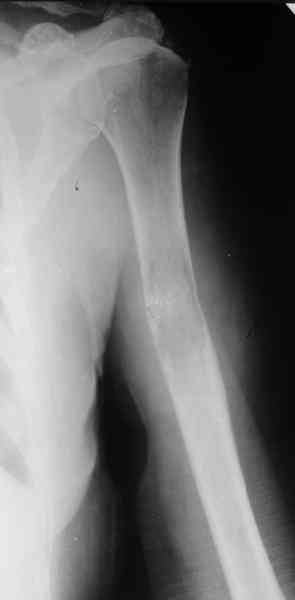

Женщина 53 лет получила патологический перелом правого плеча в феварле, и левого в марте - mts из невыясненного первичного очага.

Онкологи провели облучение, руки на косынки, время от времени наблюдают, вводили зомету.На нас вышли родственники. Состояние пациентки уже не очень, анемия (Hb -50-60 г/л), исхудалв, но асцита нет, в легких чисто. Поскольку женщина совершенно беспомощна, решили сделать остеосиннтез.

Сегодня сделали, Fixion диаметром 7,4 мм. Обе пперации продолжались по 7 мин. Картинки в приложении. Наркоз был диприваном, на спонтанном дыхании. По крайней мере, пока довольны хотя бы анестезиологи, похоже, не верили, что управимся меньше, чем за час ;-)

Гвоздик 7,4 расширяется до 11 мм. Не маловато ли, судя по снимкам?